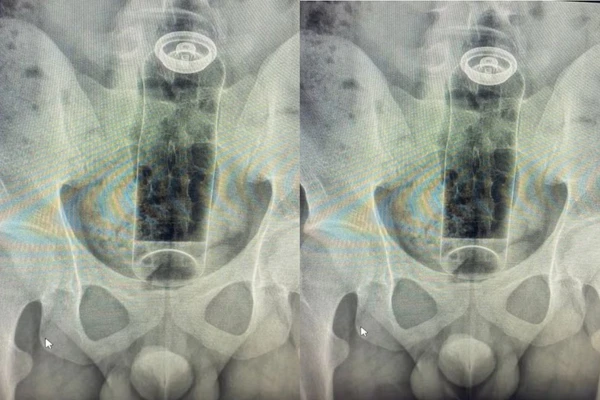

Imagens do desodorante no reto

Imagens do desodorante no reto Crédito: Reprodução

Um jovem de 19 anos precisou ser hospitalizado após um objeto ficar preso no reto durante uma prática sexual. O caso, atendido pelo cirurgião coloproctologista Daniel Brosco, envolveu a introdução de um desodorante no ânus, que acabou sendo sugado pelo intestino e não pôde ser retirado em casa.